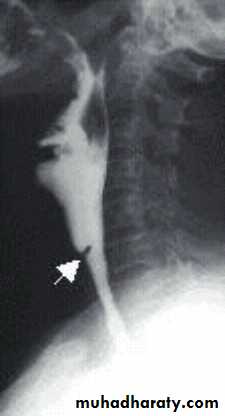

Lateral X-ray of the neck, which shows increase in prevertebral soft tissue shadow or an air-fluid level.

Lateral X-ray of the neck shows evidence of bone destruction and loss of the normal curvature of the cervical spine.Treatment